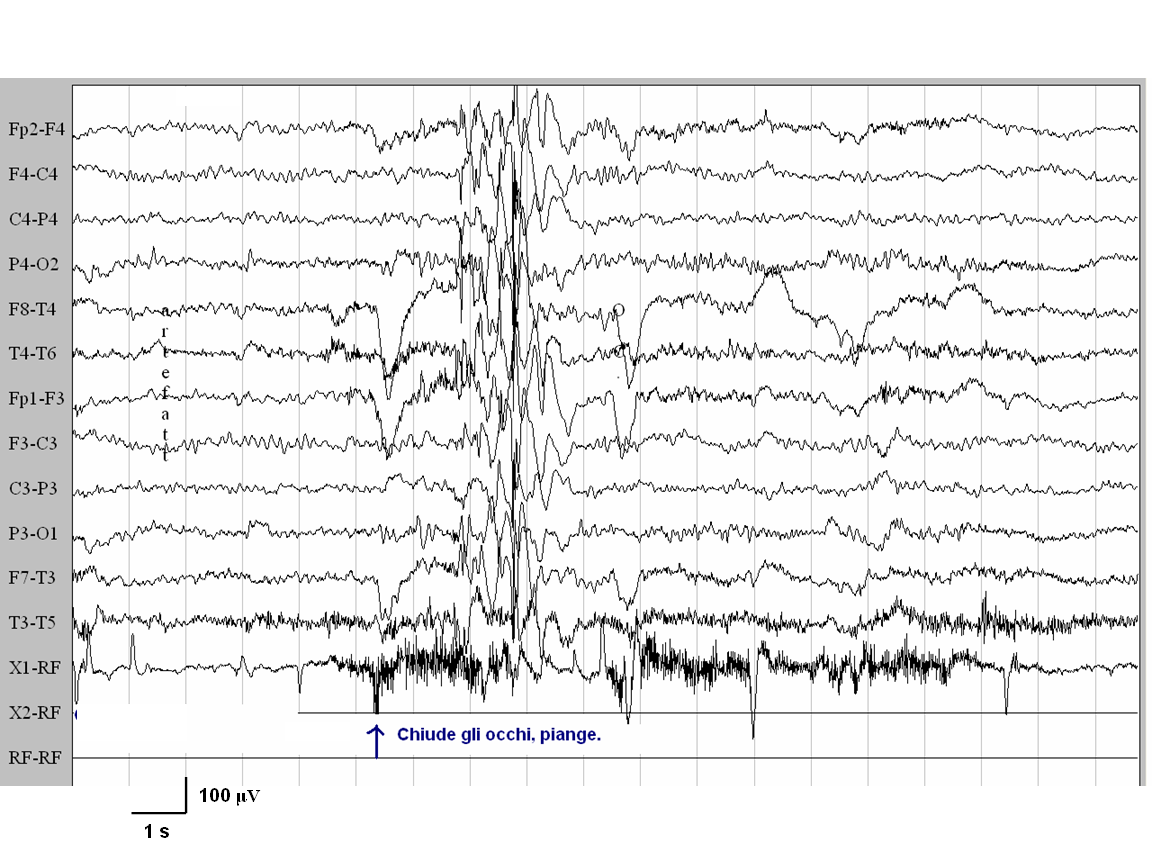

Caso

2. dopo la chiusura degli occhi compare una scarica generalizzata di

punte-onde di elevato voltaggio, a 3 cicli al secondo

È

stato effettuato uno studio EEG standard con registrazione Video-EEG

in veglia in presenza di normale luce ambientale: in entrambi i casi

entro 1 secondo dalla chiusura degli occhi sono comparse scariche

generalizzate di punta-onde, di durata inferiore ai 3 secondi, a cui

si associa clinicamente il fenomeno motorio della mioclonia

palpebrale. In entrambi i soggetti la chiusura degli occhi in

presenza di oscurità ambientale non ha provocato alcuna

scarica EEG, né alcun fenomeno clinico. La stimolazione

luminosa intermittente ha determinato risposta foto-parossistica in

entrambi i casi.